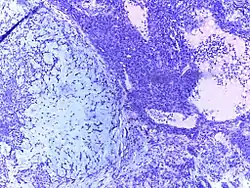

Vesicular mole | Micrograph of vesicular mole showing oedematous chorionic villus with circumferential proliferation of trophoblasts. | Category: Histopathology of chorionic villi | chorionic villi |

![]() |